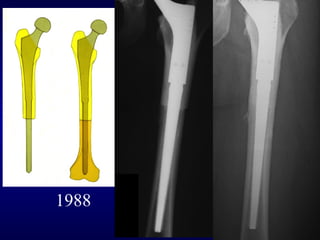

REVISIONI

FINE ANNI 80’

STELO LORD

PROBLEMI

- DOLORE ANTERIORE

di COSCIA

- “STRESS SHIELDING”

IN COMPLESSO, TECNICA

INAFFIDABILE

BOLOGNA 1988